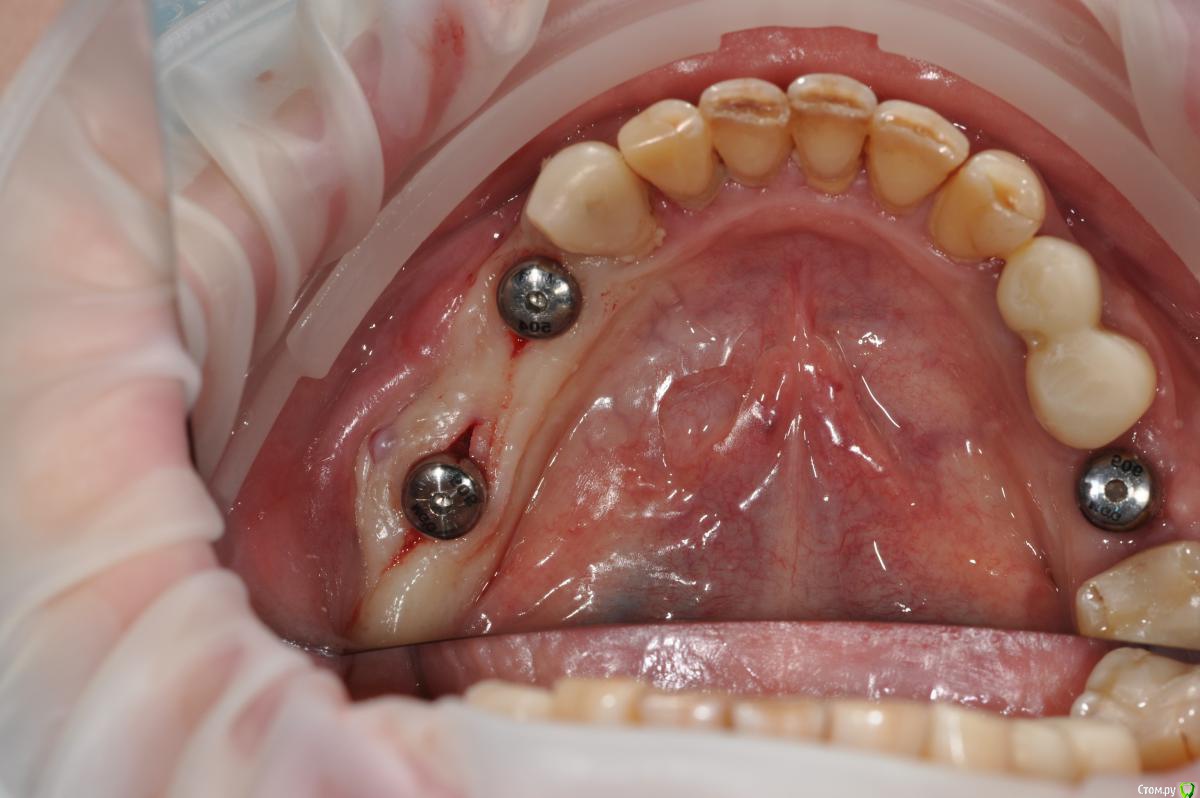

kamranchick Опубликовано 16 ноября, 2018 Поделиться Опубликовано 16 ноября, 2018 Господа, Как вы решаете вопрос с отсутствием зкпд в полном обьеме.у пациенки жалобы на то что" при поднятии языка, дна полости рта поднимается и нализиет на формирователь десны, соответственно на протезирование я пока не хочу передавать.в течении 3 недель у пациентки выросла шишка под языком в области 3 6 зуба...убрал формирователь и поставил заглушку.Видел у Ильгама как он делал зкпд, не скинете видео? не могу найтии что делать с этой шишкой и как вести пациента? спасибо 1 Ссылка на комментарий

Neilrus Опубликовано 16 ноября, 2018 Поделиться Опубликовано 16 ноября, 2018 Отсеки слизистую и подшей ниже будто сдт собираешься подсадить. С подворотом. Из сом сделай гребень. Клеить и к фдм и к зубам рядом если есть. Надо фото найти... Господа, Как вы решаете вопрос с отсутствием зкпд в полном обьеме.у пациенки жалобы на то что" при поднятии языка, дна полости рта поднимается и нализиет на формирователь десны, соответственно на протезирование я пока не хочу передавать.в течении 3 недель у пациентки выросла шишка под языком в области 3 6 зуба...убрал формирователь и поставил заглушку.Видел у Ильгама как он делал зкпд, не скинете видео? не могу найтии что делать с этой шишкой и как вести пациента? спасибодумаю до надкостницы расщепитесь со стороный переходной, подшейте как можно ниже, а к самой надкостнице полнослойный как можно плотнее пришейте, без фдм будет лучше, их потом, Каппу не забудьте на небо заранее, ибо кусочек будет нормальный.Почти похожий случай, фоткиприкрепил, не судите строго, выкладываюсь редко, прикрепленки было 1,5-2мм и то язычно 2 Ссылка на комментарий

kamranchick Опубликовано 17 ноября, 2018 Автор Поделиться Опубликовано 17 ноября, 2018 Я имею ввиду дальше или ближе по гребню.дальше нет, есть около 4-5 но там стоит имплант Ссылка на комментарий

Nazim_NV86 Опубликовано 17 ноября, 2018 Поделиться Опубликовано 17 ноября, 2018 стоит 4 мм формирователь, а реально десны мм 2-3Если добавить ССТ получишь 5мм. Вполне приемлемо. Потом расщепить и спустить слизистую. СОМ жидкотекучий использовать для того чтобы сделать преддверие. Ссылка на комментарий